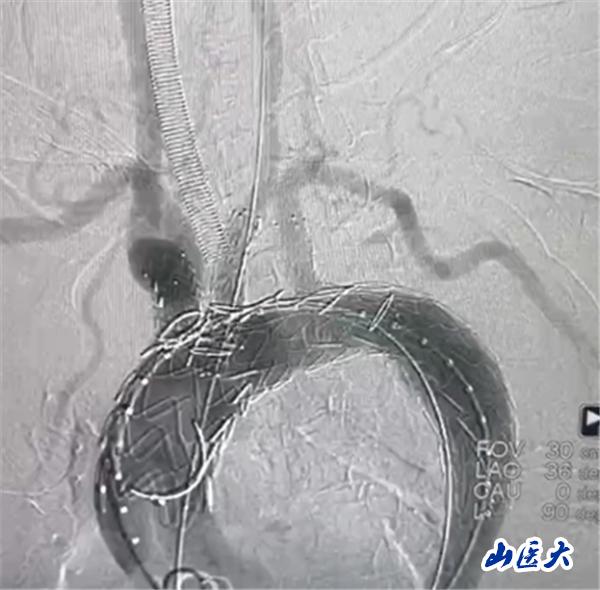

首例患者是一位55歲的女性,她患有高血壓約2年時(shí)間,平時(shí)也會(huì)規(guī)律服用多種降壓藥,但血壓控制始終不盡人意。2023年4月下午,她出現(xiàn)不明原因的頭痛,在家拔罐緩解少許便未到醫(yī)院就醫(yī),次日凌晨突感胸悶、胸背疼痛伴有呼吸困難等癥狀、家人急忙撥打了120,把患者送入醫(yī)院急診科進(jìn)行救治,醫(yī)生在急診科行胸腹主動(dòng)脈CTA時(shí),顯示主動(dòng)脈弓部-降主動(dòng)脈及腹主動(dòng)脈壁間血腫,遂收治入醫(yī)院血管外科,患者入院10天后復(fù)查血腫仍未有改善,依然伴有胸背部疼痛等不適,如不進(jìn)一步處理,可能發(fā)展為夾層危及生命,患者及家屬經(jīng)過(guò)與醫(yī)生團(tuán)隊(duì)了解溝通,決定進(jìn)行創(chuàng)傷小、恢復(fù)快的介入手術(shù)治療。張瑋教授、符偉國(guó)教授、董紅霖教授及其血管外科團(tuán)隊(duì)(閆盛、常文凱、田琴琴)共同商討手術(shù)方案,最終確定使用Zipper?一體式主動(dòng)脈弓覆膜支架系統(tǒng),行胸主動(dòng)脈覆膜支架腔內(nèi)隔絕術(shù)+無(wú)名動(dòng)脈、左頸總動(dòng)脈、左鎖骨下動(dòng)脈分支重建術(shù)為患者進(jìn)行治療。董紅霖教授及其血管外科團(tuán)隊(duì)根據(jù)患者術(shù)前頭顱CT平掃提示雙側(cè)側(cè)腦室旁缺血灶,血壓控制不穩(wěn)定,屬夾層壁間血腫非典型夾層等風(fēng)險(xiǎn)點(diǎn),制定了完整的手術(shù)方案,術(shù)中經(jīng)股動(dòng)脈置入Zipper支架主體,經(jīng)預(yù)留導(dǎo)絲超選無(wú)名動(dòng)脈,并確保主體支架對(duì)位準(zhǔn)確,順利置入左頸總動(dòng)脈、左鎖骨下動(dòng)脈支架,重建弓上三分支。手術(shù)過(guò)程非常順利。術(shù)后觀察主動(dòng)脈及分支覆膜支架定位準(zhǔn)確;無(wú)內(nèi)漏;分支支架通暢,動(dòng)脈供血正常。

術(shù)中造影結(jié)果

術(shù)后效果